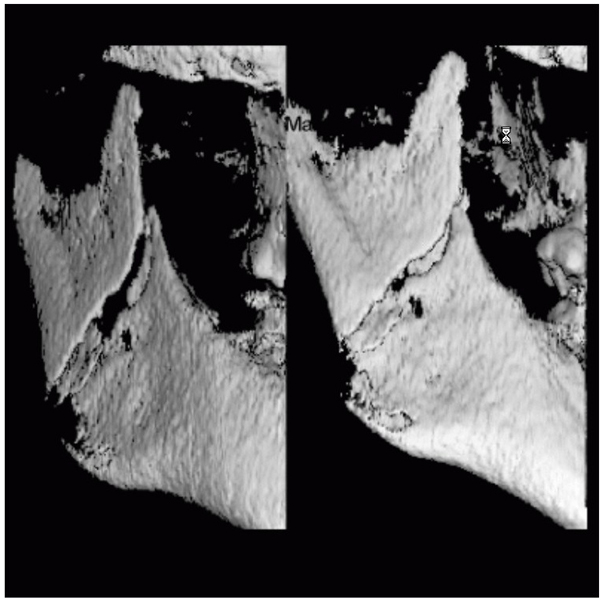

3D DVT - NewTom

Je speciální zubní digitální tříprostorový tomograf (3D), který umožňuje na základě jediného

snímkování vytvořit všechny typy RTG zobrazení, které jsou pro lékaře potřebné. Díky používané technologii tzv. „kuželového paprsku“ a speciálním senzorům je

výrazně zmenšená dávka záření - o více jak 80% proti klasickému CT vyšetření. To je významné zejména u dětí. Pomocí tohoto přístroje je možné zjisti skutečnou situaci v čelistních kostech pacienta tedy množství kosti - můžeme změřit skutečnou šířku i výšku kosti, i kvalitu kosti (hustotu) v místě uvažované implantace. 3D (tříprostorové) zobrazení umožňuje zvýšit prostorovou představu operatéra ještě před vlastní operací a zároveň pacientovi lépe objasnit a ukázat oblast plánovaného zavedení implantátu.

Pacient „neumí číst“ RTG snímky, ale díky 3D zobrazení vidí „svoji skutečnou čelist“

- např. jak je nízká či úzká, vidí průběh nervu nebo velikost čelistní dutiny, což mu umožní i pochopení nutnosti v některých případech provést pomocné zákroky ještě před vlastním zavedením implantátu (viz. kostní štěp, sinus lift, kostní granulát...).

Vyšetření pomocí tohoto přístroje používáme i ve stomatochirurgii (zlomeniny čelistí, zuby moudrosti, cysty, onemocnění čelistního kloubu), ortodoncii (retinované zuby, nadpočetné zuby), parodontologii atd.